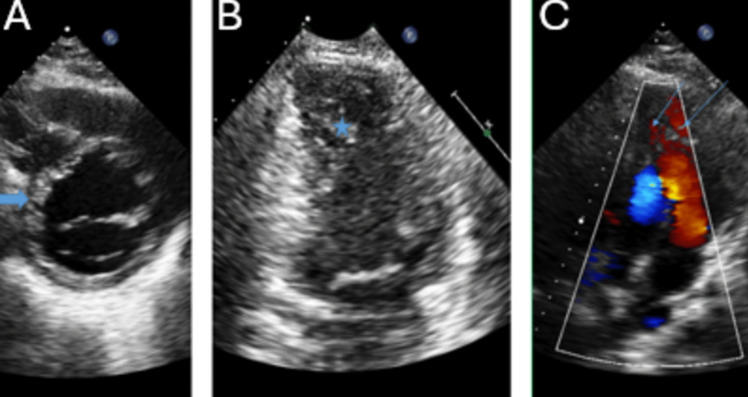

Purpose of review: The purpose of this review is to highlight the utility of echocardiography in the diagnosis and management of cardiomyopathies.

Recent findings: Echocardiographic parameters function synergistically to guide decision-making ranging from early detection of disease and screening to risk stratification of complex disease. The collective wealth of information available from 2D/3D assessment, Doppler, diastology and strain makes echocardiography an invaluable decision aid.